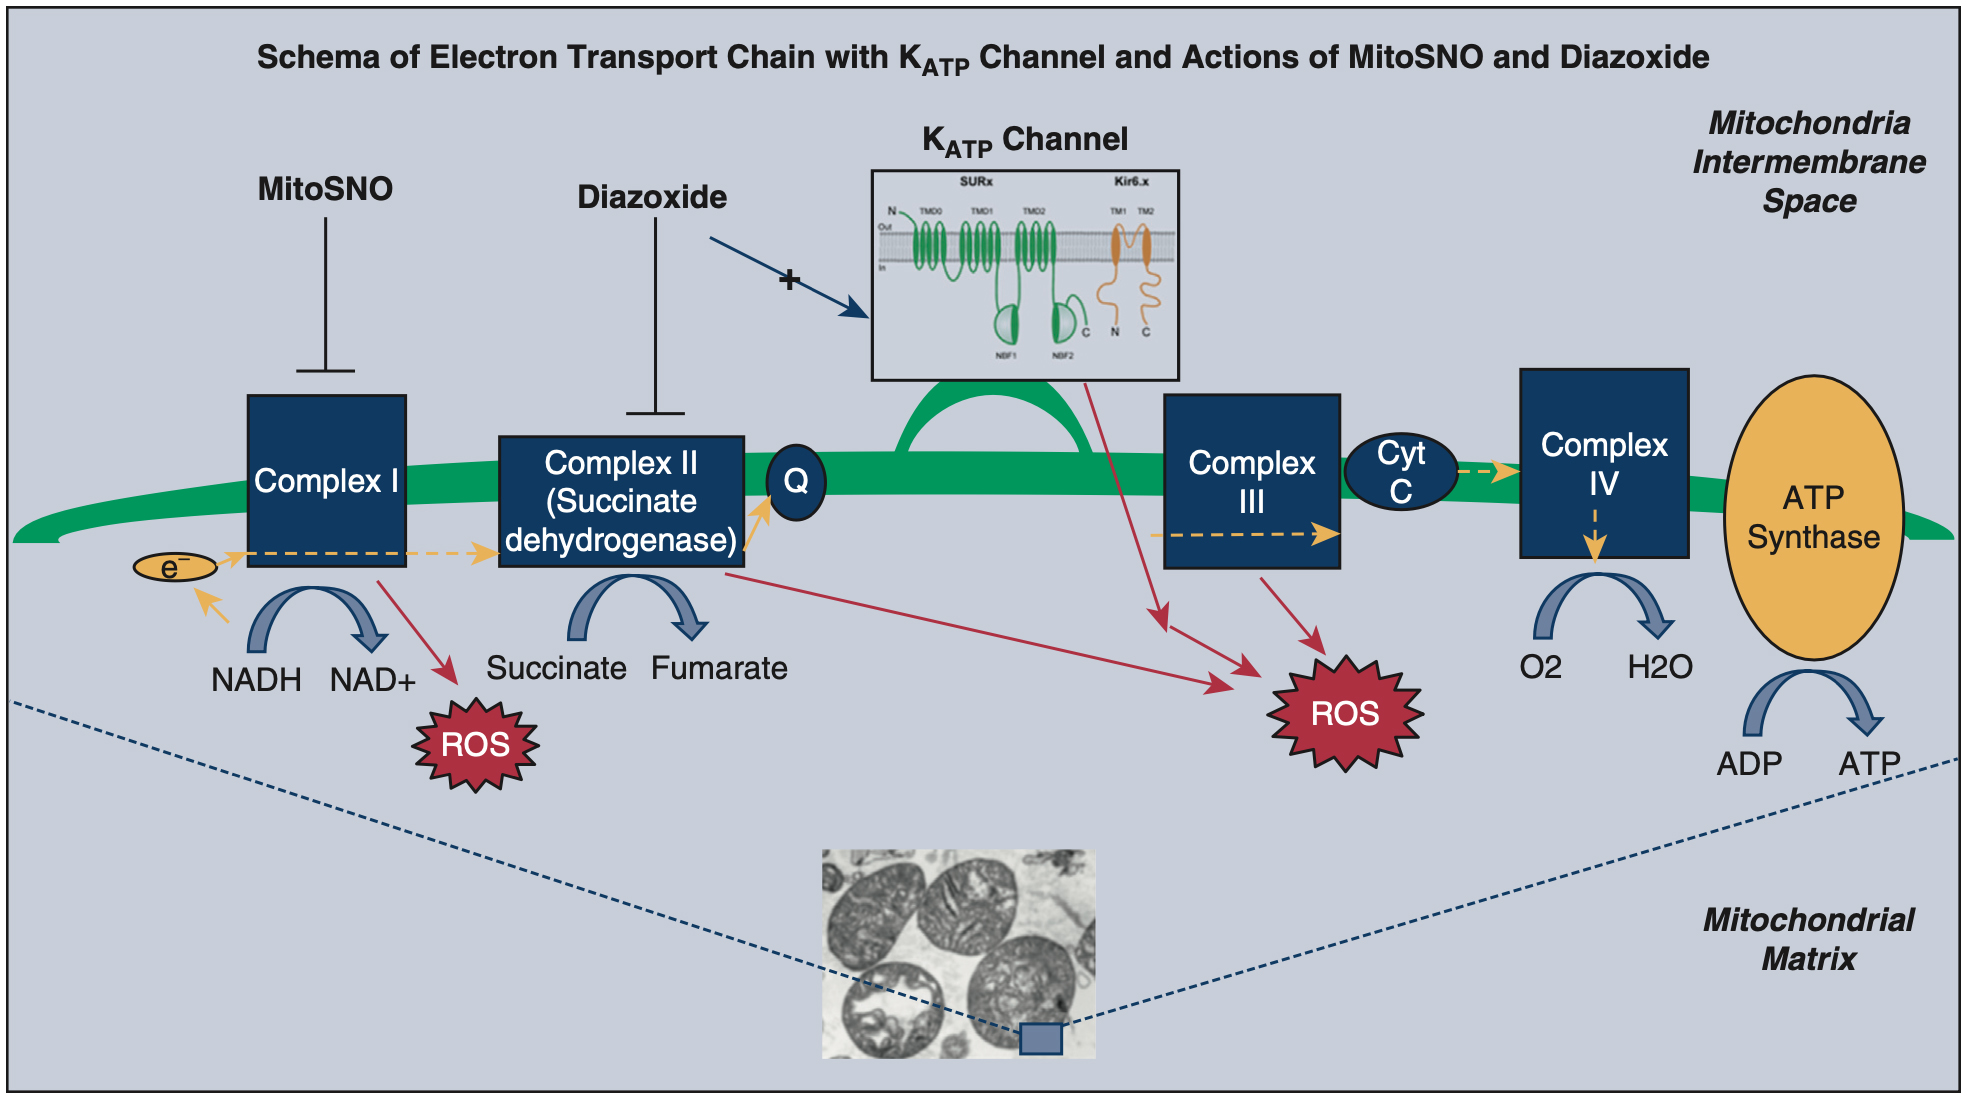

Reactive oxygen species mimic IPC (attributed to activity at a KATP channel) and antioxidants block IPC[114,115]. The role of ROS was investigated as a potential cardioprotective mechanism of diazoxide[67]. Diazoxide and pinacidil increased ROS in cardiomyocytes, and this increase was blocked with the co-administration of 5-hydrodecanoate or an antioxidant, supporting the hypothesis that ROS are involved in cardioprotection facilitated by mitoKATP channels[114]. In isolated perfused rat hearts, ROS generation prior to ischemia onset contributed to the cardioprotection of both IPC and diazoxide[125]. In animal models, glutathione (an antioxidant) administered before ischemia prevented cardioprotection by diazoxide, via prevention of inhibition of SDH or the inhibition of ROS formation[60]. Similarly, a mitochondrial-targeted antioxidant that inhibits mitochondrial enzyme complex I MitoSNO (given at reperfusion) reduced cardioprotection by diazoxide, suggesting an interplay at the mitochondrial level [Figure 1][126]. Data published in 2019 provided further evidence that mitoKATP is important for redox homeostasis by showing that diazoxide results in increased ROS in wild-type mice, but not in cells lacking proposed mitoKATP channel subunits[45].

Figure 1. Electron transport chain with KATP channel and actions of MitoSNO and diazoxide. The schema simplifies the activity of the inner membrane of the mitochondrion, including the proposed KATP channel and electron transport chain. At the bottom of the figure, a photo taken by electron microscopy from the Lawton laboratory, of individual mitochondria. In the schema, diazoxide is depicted as having an inhibitory effect on Complex II (succinate dehydrogenase) while activating the KATP channel. The cardioprotection by diazoxide may occur due to either of the mechanisms or another mechanism. MitoSNO has an inhibitory effect on Complex I, which prevents SDH accumulation, and this is thought to be the cardioprotective mechanism of MitoSNO. While each is cardioprotective via these mechanisms, these two agents have a synergistic negative effect[126]. This figure is used with permission from Elsevier (obtained September 4, 2023, license number 5621920353581)[126]. MitoSNO: Mitochondria-targeted S-nitrosating agent; NADH: nicotinamide adenine dinucleotide, reduced form; NADþ: nicotinamide adenine dinucleotide, oxidized form; ROS: reactive oxygen species; ATP: adenosine triphosphate; ADP: adenosine diphosphate; Cyt C: cytochrome C.